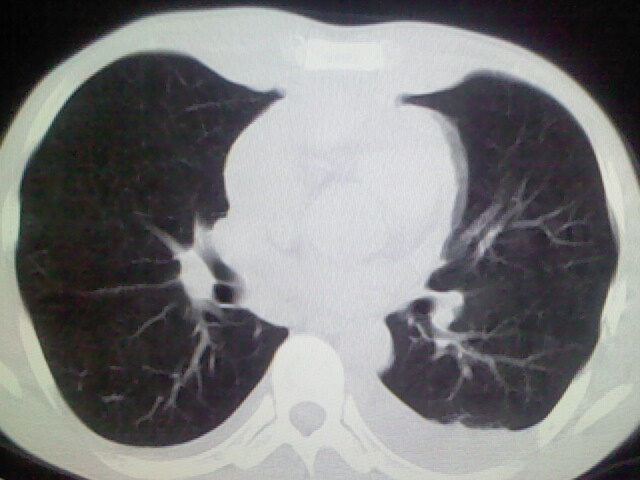

以下是引用杀毒软件在2008-9-3 6:11:00的发言:[br]侵袭性胸腺瘤------一般不侵到气管旁[br][br]考虑----纵隔淋巴瘤,心包及胸膜受累

以下是引用随光逐影在2008-9-3 7:07:00的发言:[br]1)考虑淋巴瘤可能。2)双侧胸腔积液(以左侧为甚)。3)心包积液。